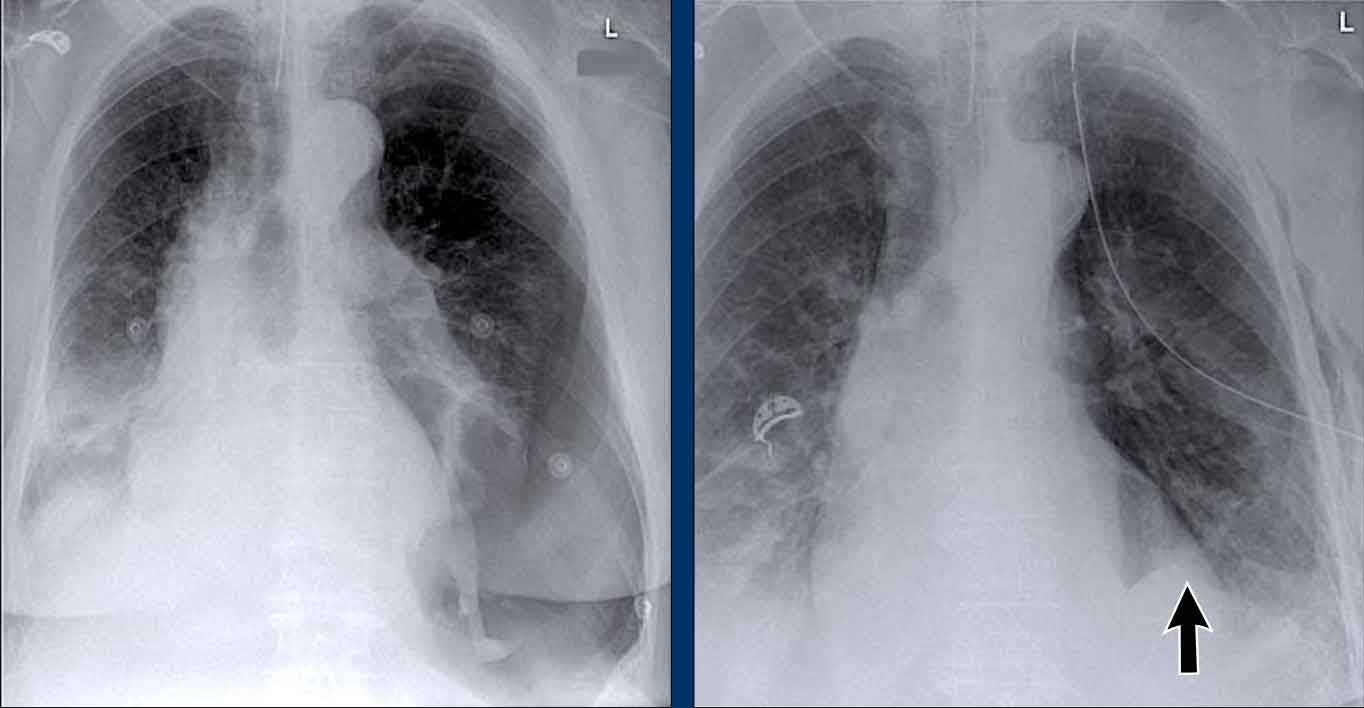

Case Example: Subtle Signs of Congestive Heart Failure

Begin by reviewing these current chest radiographs.

Based solely on these images, one might suspect congestive heart failure (CHF), though the findings are subtle.

Now review the previous study…

Scrolling between the current and prior films significantly increases diagnostic confidence in your diagnosis of congestive heart failure.

Key comparative findings include:

• Cardiac size: Slightly increased compared to the previous study; however, cardiomegaly was already present.

• Pulmonary vasculature: Mild vascular engorgement suggesting elevated pulmonary venous pressure.

• Interstitial markings: Subtle signs of interstitial edema .

• Pleural effusions: Bilateral small effusions, with subtle changes in the inferoposterior borders of the lower lobes, suggesting fluid accumulation.